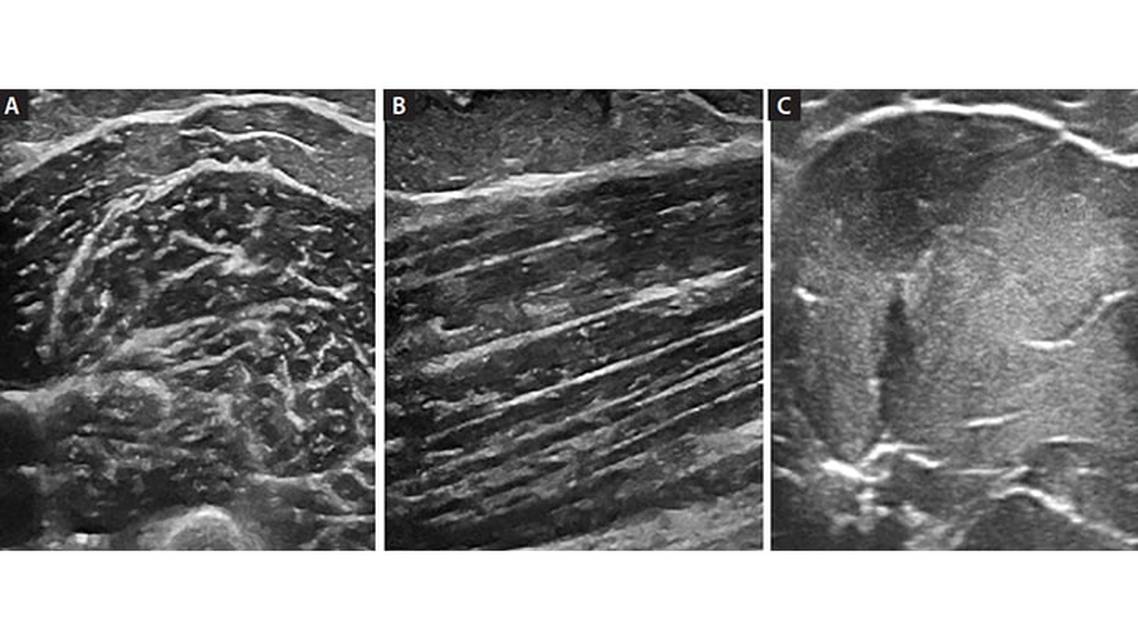

Muscle imaging was among the first uses of NMUS and continues to expand with applications for muscular dystrophies, myopathies, motor neuron disease, and other muscle disorders. Ultrasound of normal skeletal muscle has a heterogeneous appearance that is fairly hypoechoic (dark) interspersed with hyperechoic (bright) areas, representing the normal fibrous connective tissue within the muscle. In the transverse plane, there is a “starry-sky” appearance because these fibrous structures are viewed in cross-section against the darker background of muscle fibers (Figure 1A). In the longitudinal plane, the bright fibrous structures run lengthwise, streaking across the darker muscle fibers (Figure 1B).

Characteristic ultrasound findings of muscular dystrophies include loss of normal heterogeneous appearance as muscle is replaced by fatty fibrous tissue in affected muscles. Dystrophic muscles take on a bright, homogenous appearance.5 Deep tissue reflections are lost or attenuated in severely affected dystrophic muscles. Similar changes of increased echogenicity may be seen in acute inflammatory myopathies, but in contrast to muscular dystrophies, there are often preserved deep-tissue reflections (Figure 1C).6